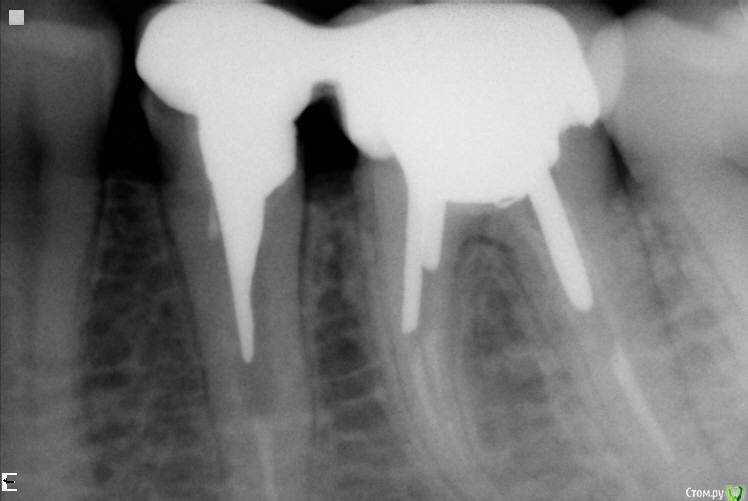

Girl Опубликовано 13 июля, 2017 Поделиться Опубликовано 13 июля, 2017 Доброе утро.6 месяцев назад в клинику обратился пациент с жалобами на боль между 36и 37. 36 резорциненный.Перелечка в 4 посещения. На сколько возможно. Сейчас снова жалобы на боль в 36, невозможно дотронуться даже языком. На сниме изменений в периапикальных тканях вроде нет. Все как и было 6 месяцев назад.Снимки до и после 6 месяцвВозможно наличии трещины? Ссылка на комментарий

vse32 Опубликовано 13 июля, 2017 Поделиться Опубликовано 13 июля, 2017 Снимок после - периапикальная область обрезана.Но можно заподозрить трещину в бифуркации. Хотя, только заподозрить.Причина болей 6 месяцев назад и сейчас - это точно не одна и та же трещина. Трещины не успокаиваются. Да и если бы трещина существовала бы полгода - это бы отразилось на состоянии костной ткани.Так что, это либо свежая трещина, либо еще что-то. Ссылка на комментарий

Паращук Роман Опубликовано 14 июля, 2017 Поделиться Опубликовано 14 июля, 2017 до есть периапикалка на 6ке. Ссылка на комментарий